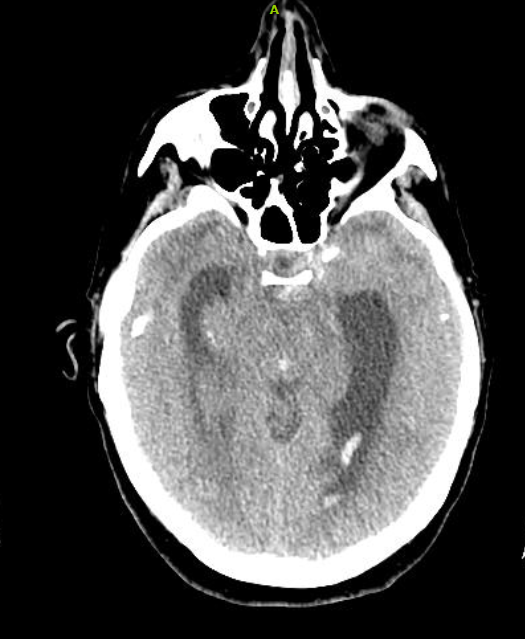

Neurogenic stunned myocardium is a triad of reversible left ventricular dysfunction, electrocardiogram changes and elevation of cardiac enzymes. Clinically, this provides diagnostic challenges in the setting of subarachnoid hemorrhage (SAH) due to the diagnostic uncertainty. The pathophysiological mechanisms for neurogenic stunned myocardium have included hypothalamic and myocardial perivascular lesions. More recently, alternative research has focused on myocardial microvascular dysfunction and genetic polymorphisms. Management has remained largely supportive with case reports citing the benefits of inotropes and intra-aortic balloon pumps in the setting of cardiogenic shock complicating NSM. When NSM follows SAH there are numerous complications, including pulmonary edema, arrhythmias and prolonged intubation, which can impact outcomes and increase morbidity and mortality. This highlights the need for accurate and timely diagnosis of NSM which has remained a clinical challenge. We report a case of a 52-year-old patient who presented to the ICU with complaints of atypical chest pain without neurologic complaints or lateralizing symptoms. She was admitted to the ICU for ongoing chest pain with concurrent ECG T-wave inversions. Within 24 hours she developed lateralizing neurologic signs and altered mental status with subsequent imaging revealing evidence of a SAH. We describe characteristics and outcomes of NSM in this patient with aneurysmal associated SAH.References